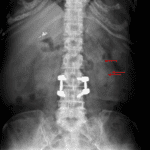

Age: 75

Sex: Female

Indication: Follow up renal stones

- Hepatomegaly

- Right upper quadrant surgical clips

- L3-L4 pedicle screw and rod fixation and interbody graft at L4-L5